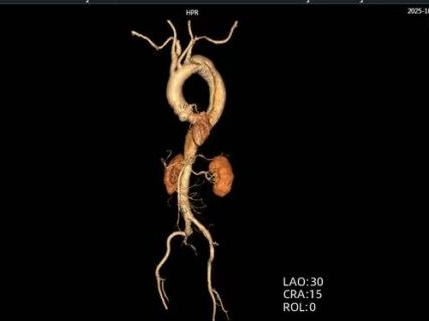

48岁男性,突发上腹剧烈疼痛伴有大汗淋漓,既往多年高血压病史。

时间就是生命。医生会结合症状,快速进行以下检查:医院会根据CT血管成像(CTA)进行诊断。如确诊为主动脉夹层,则会进行紧急处理,立即镇痛、控制血压和心率(如静脉注射β受体阻滞剂)。

主动脉腔内修复术:微创治疗。通过大腿根部的股动脉,将一个覆膜支架送入主动脉夹层部位,像打补丁一样覆盖住内膜破口,使血流不再进入假腔,促进假腔血栓化愈合。